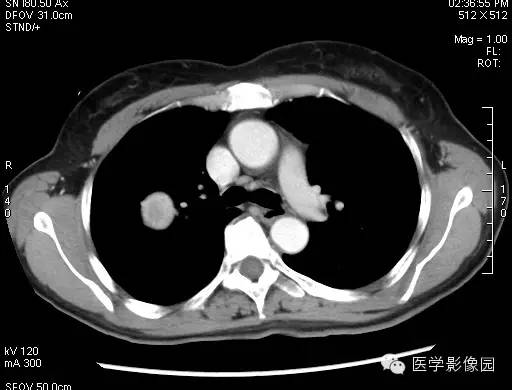

动脉期的增强在中等以上,静脉期增强在动脉期的程度上有更深程度的强化,当肿瘤边缘不清晰时,就有呈现浅分叶、胸膜凹陷、短毛刺等现象,边缘清楚、光整,多数形态规则、少数可见浅分叶,无毛刺、空洞,无卫星灶,密度均匀,偶有钙化,无胸膜凹陷征。CT增强扫描显示病灶中等以上均匀或不均匀强化,且存在延迟强化现象,对PSH具有一定的诊断价值。